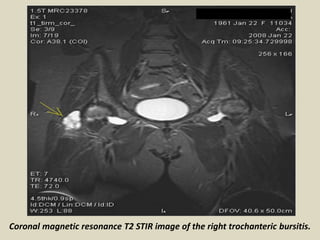

Coronal magnetic resonance T2 STIR image of the right trochanteric bursitis.

Bursitis (green arrows) appears as a fluid collection(decreased T1 signal, increased

(T2signal). Iliotibial band (thin green arrows), greater trochanter (blue arrows).